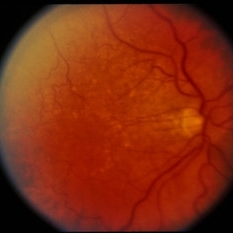

RPE Tear

RPE Tear

Sep 9 2014 by David Callanan, MD

78-year-old male, RPE tear.

Condition/keywords: retinal pigment epithelium